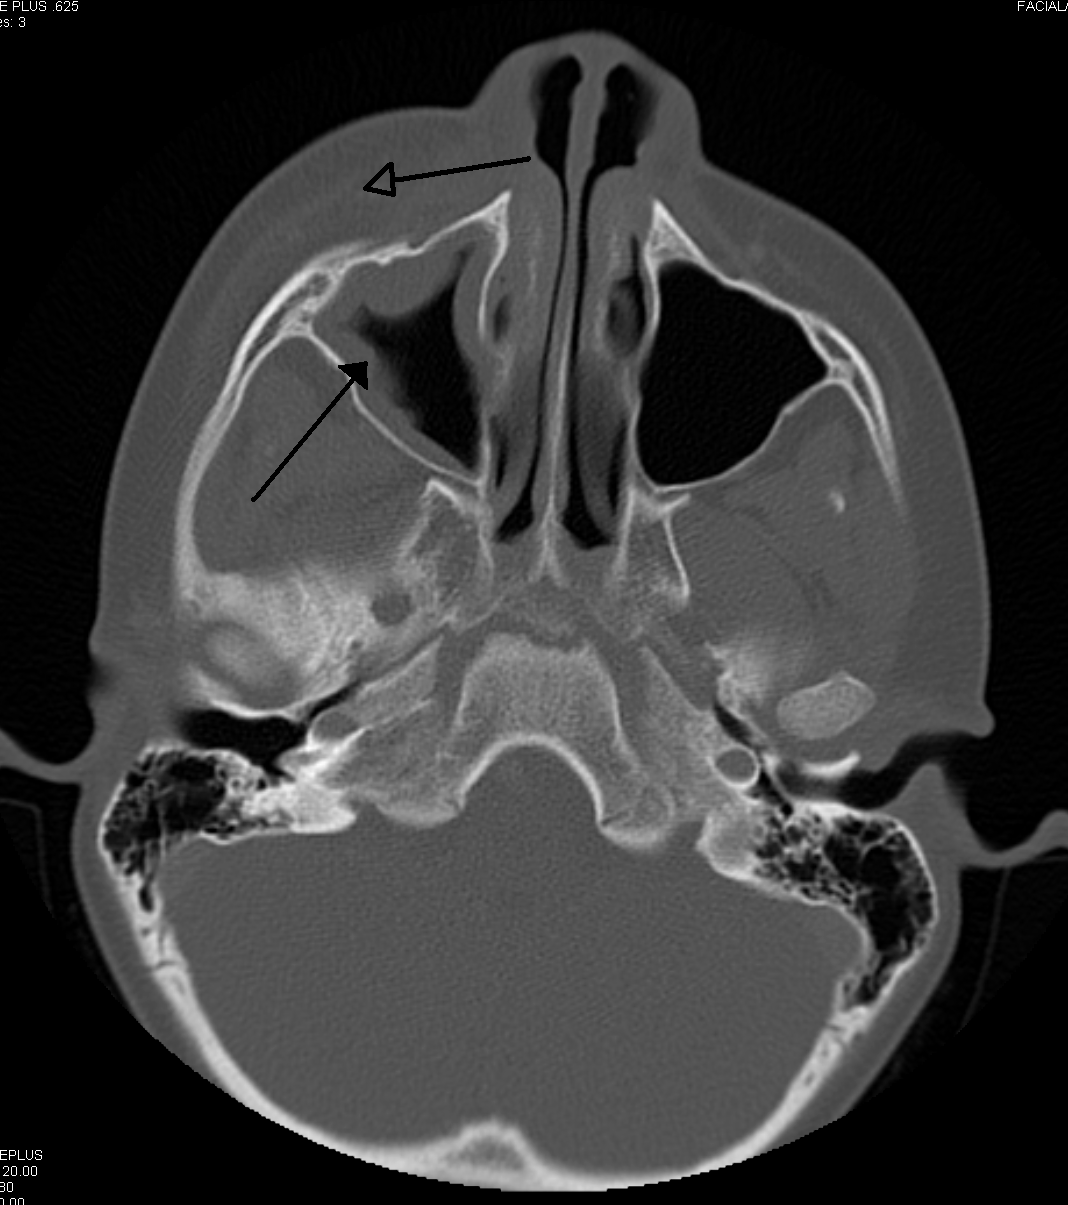

부비동염의 진단은 주로 콧물의 성상, 양, 그리고 호흡기 증상을 통해 이루어진다. 알레르기가 의심될 경우 알레르기 검사를 시행하며, 단층 촬영(CT)을 실시하기도 한다.[60] 의료 제공자는 관찰 대기를 통해 세균성 부비동염과 바이러스성 부비동염을 구별한다. 증상이 악화되지 않은 채 10일 미만 지속되면 바이러스성 감염으로 추정한다.[60] 반면, 증상이 10일 이상 지속되거나 그 사이에 악화되면 세균성 부비동염으로 간주한다.[63] 치아 통증과 구취 또한 세균성 질환을 시사하는 지표이다.[62]

합병증이 없다면 X-ray, CT, MRI와 같은 영상 촬영은 일반적으로 권장되지 않는다.[63] 부비동염으로 인한 통증은 상악 치아의 치수염(치통)으로 인한 통증과 혼동될 수 있으며, 그 반대의 경우도 마찬가지이다. 머리를 앞으로 숙일 때 통증이 심해지는 것은 부비동염을 치수염과 구별하는 특징적인 증상이다.

상악 부비동염의 경우, CBCT와 같은 제한된 범위의 영상 촬영은 치근단 방사선 사진보다 치아가 부비동염의 원인인지 더 정확하게 감지할 수 있다. 관상 CT 사진 또한 유용하다.[93]

- X선 촬영, 컴퓨터 단층 촬영(CT)으로 부비동 내 고름 축적 여부를 확인한다.

만성 부비동염이 12주 이상 지속되면 CT 스캔을 받는 것이 좋다.[63] CT 스캔에서 급성 부비동 분비물은 10~25 하운스필드 단위(HU)의 방사선 밀도를 나타내지만, 만성 상태에서는 점성이 증가하여 방사선 밀도가 30~60 HU가 된다.[64]